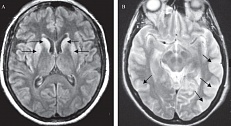

В документе говорится о том, что приобретенная миастения является патологией нервномышечной проводимости, возникающей в результате связывания антител с компонентами нервномышечного синапса, чаще всего, с ацетилхолиновым рецептором. Частота заболеваемости находится в диапазоне 0,3-2,8 на 100 000 населения, и по оценкам в мире миастенией страдают более 700 000 человек.